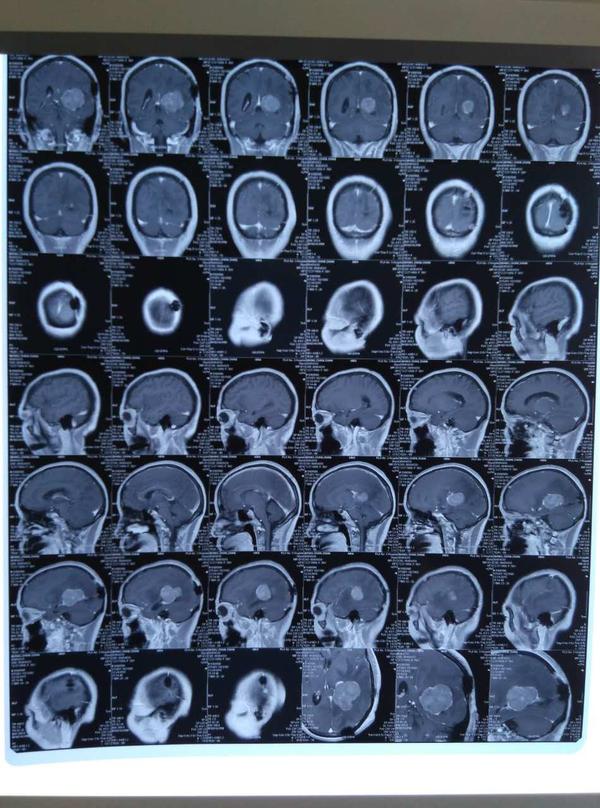

患者,女性,今年56岁,主因头痛、呕吐、视力下降严重就诊,后行脑瘤切除手术。既往有乳腺癌病史,已手术切除。

患者半年前因头痛、呕吐、视力下降严重就诊于附近某医院,行头颅MR平扫+CT示颞叶占位性病变,考虑为胶质瘤,入院后在全麻下进行颞叶占位性病变切除手术,术后病理胶质瘤2级。一周前,患者精神差,伴左侧上眼睑下垂,视力下降严重。为治疗,就诊于第四军医大学唐都医院神经外科,经影像学检查后诊断:胶质瘤复发,肿瘤较大,贾主任结合患者病史建议患者住院进行全面仔细检查,进行二次手术治疗。

复发的胶质瘤与原来的肿瘤相比有很大不同:其一、复发胶质瘤的恶性程度一般会增高,原来二级的变成三级,原来三级的变成四级,称为肿瘤演进;其二、生长速度更快;其三、血供变得更丰富;其四、复发肿瘤对原先敏感的化疗药物可能变得耐药了。由于这些重要变化,复发胶质瘤的治疗方案的决策很复杂。